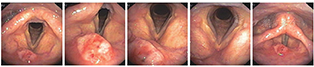

电子喉镜检查:位于"会厌结节下凹陷"上方[2],会厌喉面中央偏右,可见菜花样广基新生物,约1.0 cm×1.0 cm×0.5 cm,质脆,部分覆白色苔膜,边界不清,肿瘤未侵及双侧室带及前连合(图1)。病理检查提示为:中分化鳞状细胞癌;颈部淋巴结彩超检查:双侧颈部淋巴结可见,淋巴门清晰,未见明显异常淋巴结;喉部CT:会厌结节偏右局部增厚,密度增高,未见异常淋巴结及会厌前间隙受侵及征象(图2)。术前血常规、凝血项及生化全项等常规检查未见异常;肝胆脾超声及肺部CT未见异常。

术后对患者进行定期密切随访,2个月电子喉镜检查见喉腔术区愈合良好,苔膜基本脱落,局部有瘢痕挛缩;嗓音评估及颈部淋巴结超声:与术前对比均无明显改变。从复查视频可以看到,喉腔整体形态和功能恢复较快,没有明显术后杓会厌襞水肿,优于传统的水平半喉切除术,随访视频见视频2。